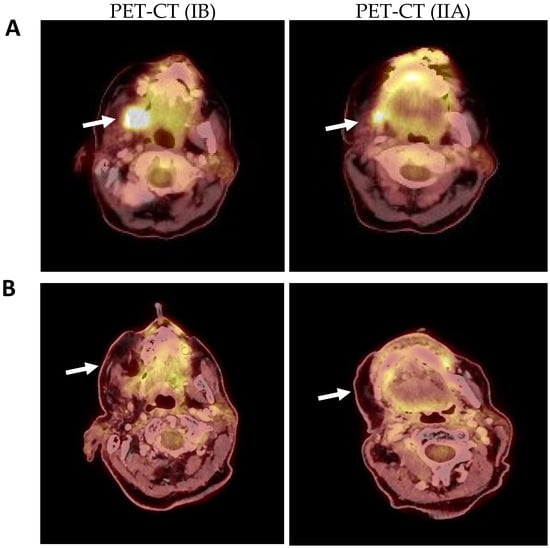

4.3. Positron Emission Tomography-Computed Tomography